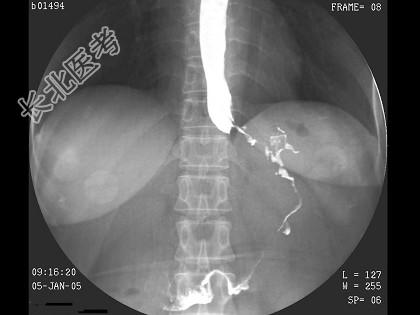

- 单项选择题女,53岁, 进行性吞咽困难伴呕吐,吐黏液半月, 结合图像,最可能的诊断为 ( )

A、食管癌

B、贲门癌

C、食管静脉曲张

D、贲门失弛缓

E、胃底癌